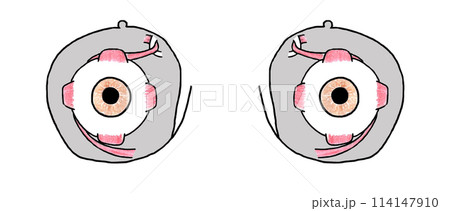

DENTALISH歯科英語チャンネル🦷 ▶︎Anatomical plane 解剖学的平面CTなどでよく見かける三次元平面に関してです! ↔️体を左右に分ける面 矢状面:Sagittal plane 縦断面:Longitudinalplane ↕️体を上下に分ける面 軸断面:Axial planeInstagram。

肩胛骨冠状面解剖图PNG图片素材下载_图片编号4075467-PNG素材网。